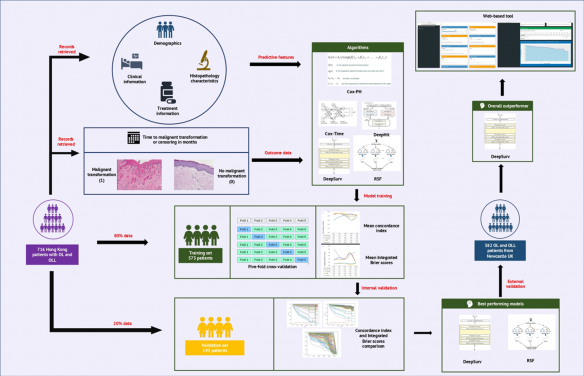

Researchers from the Faculty of Dentistry and the Li Ka Shing Faculty of Medicine, the University of Hong Kong (HKU); Department of Pathology, Queen Mary Hospital, HK; and College of Medicine and Dentistry, James Cook University, Queensland collaborated to develop a web platform that can be applied to automatically generate an individualized prediction of the risk of oral cancer occurrence in those with OL or OLM for up to 20 years following diagnosis.

The results are published in the journal Cancers in an article entitled “Deep learning predicts the malignant-transformation-free survival of oral potentially malignant disorders”.

The freely available web tool, based on the artificial intelligence algorithm ‘DeepSurv’ was trained and tested with data from patients with OL/OLM treated in Hong Kong (716 patients) and Newcastle Upon Tyne, UK (382 patients). As the patients have already been under review for many years, their true risk levels were already known, and the study showed that the artificial intelligent model was able to accurately predict their risk levels at different time points during their follow-up hospital visits.

The DeepSurv algorithm was selected due to its superior performance for the use of routine demographic, clinical, pathological, and treatment information of these patients for cancer risk prediction following a series of validation exercises.

On a validation subset of the Hong Kong cohort, ‘DeepSurv’ was able to predict the correct cancer risk level for 95% of the cases. This was according to an integrated Brier score of 0.04, with a score below 0.25 generally depicting a tool that may be useful in real-world applications.

The algorithm is further able to generate correct risk levels for 82% of the patients in the British cohort which suggests its utility in other populations as well.

To expatiate on how the interactive web tool functions, it requires 26 pieces of information on the demography, clinical and pathological description of the disease, and treatment received by the OL/OLM patient. The predicted output from the web tool includes a curve from which the different risk levels (vertical axis) can be visualized at each time point (horizontal axis). These predicted risk levels have been shown to be accurate up to 17 years from the time that the information was entered.

“While the web tool has been found promising based on our validation exercises, users should know that it is still primarily a research-based tool and requires further prospective optimization,” said Dr Richard Su, Clinical Associate Professor in Oral and Maxillofacial Surgery (OMFS), Faculty of Dentistry, HKU, who led the study.

“Since cancer development involves many alterations at the molecular level that may occur before disease diagnosis, we will in the future optimize the web tool by including information on molecular biomarkers for cancer development in OL and OLM.” Dr Su added. It is expected that the inclusion of the information in the web tool will improve the precision of the predicted risk estimates. The updated web tool will then be evaluated for its clinical efficacy and its impact in the care of OL and OLM in a clinical trial.